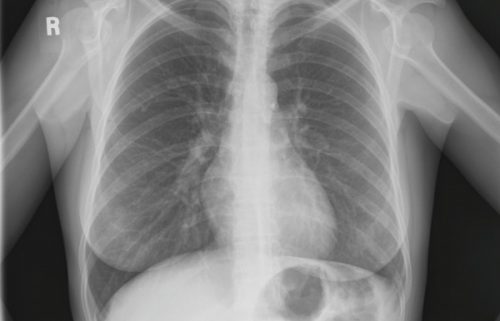

Chest x-rays are the most common medical imaging examinations. They produce an image of your heart and lungs. A chest radiograph is performed as part of routine physical exam or to reveal/rule out conditions like pneumonia, congestive heart failure, tuberculosis or other lung and heart conditions. Here is how to prepare for a Chest X-Ray.